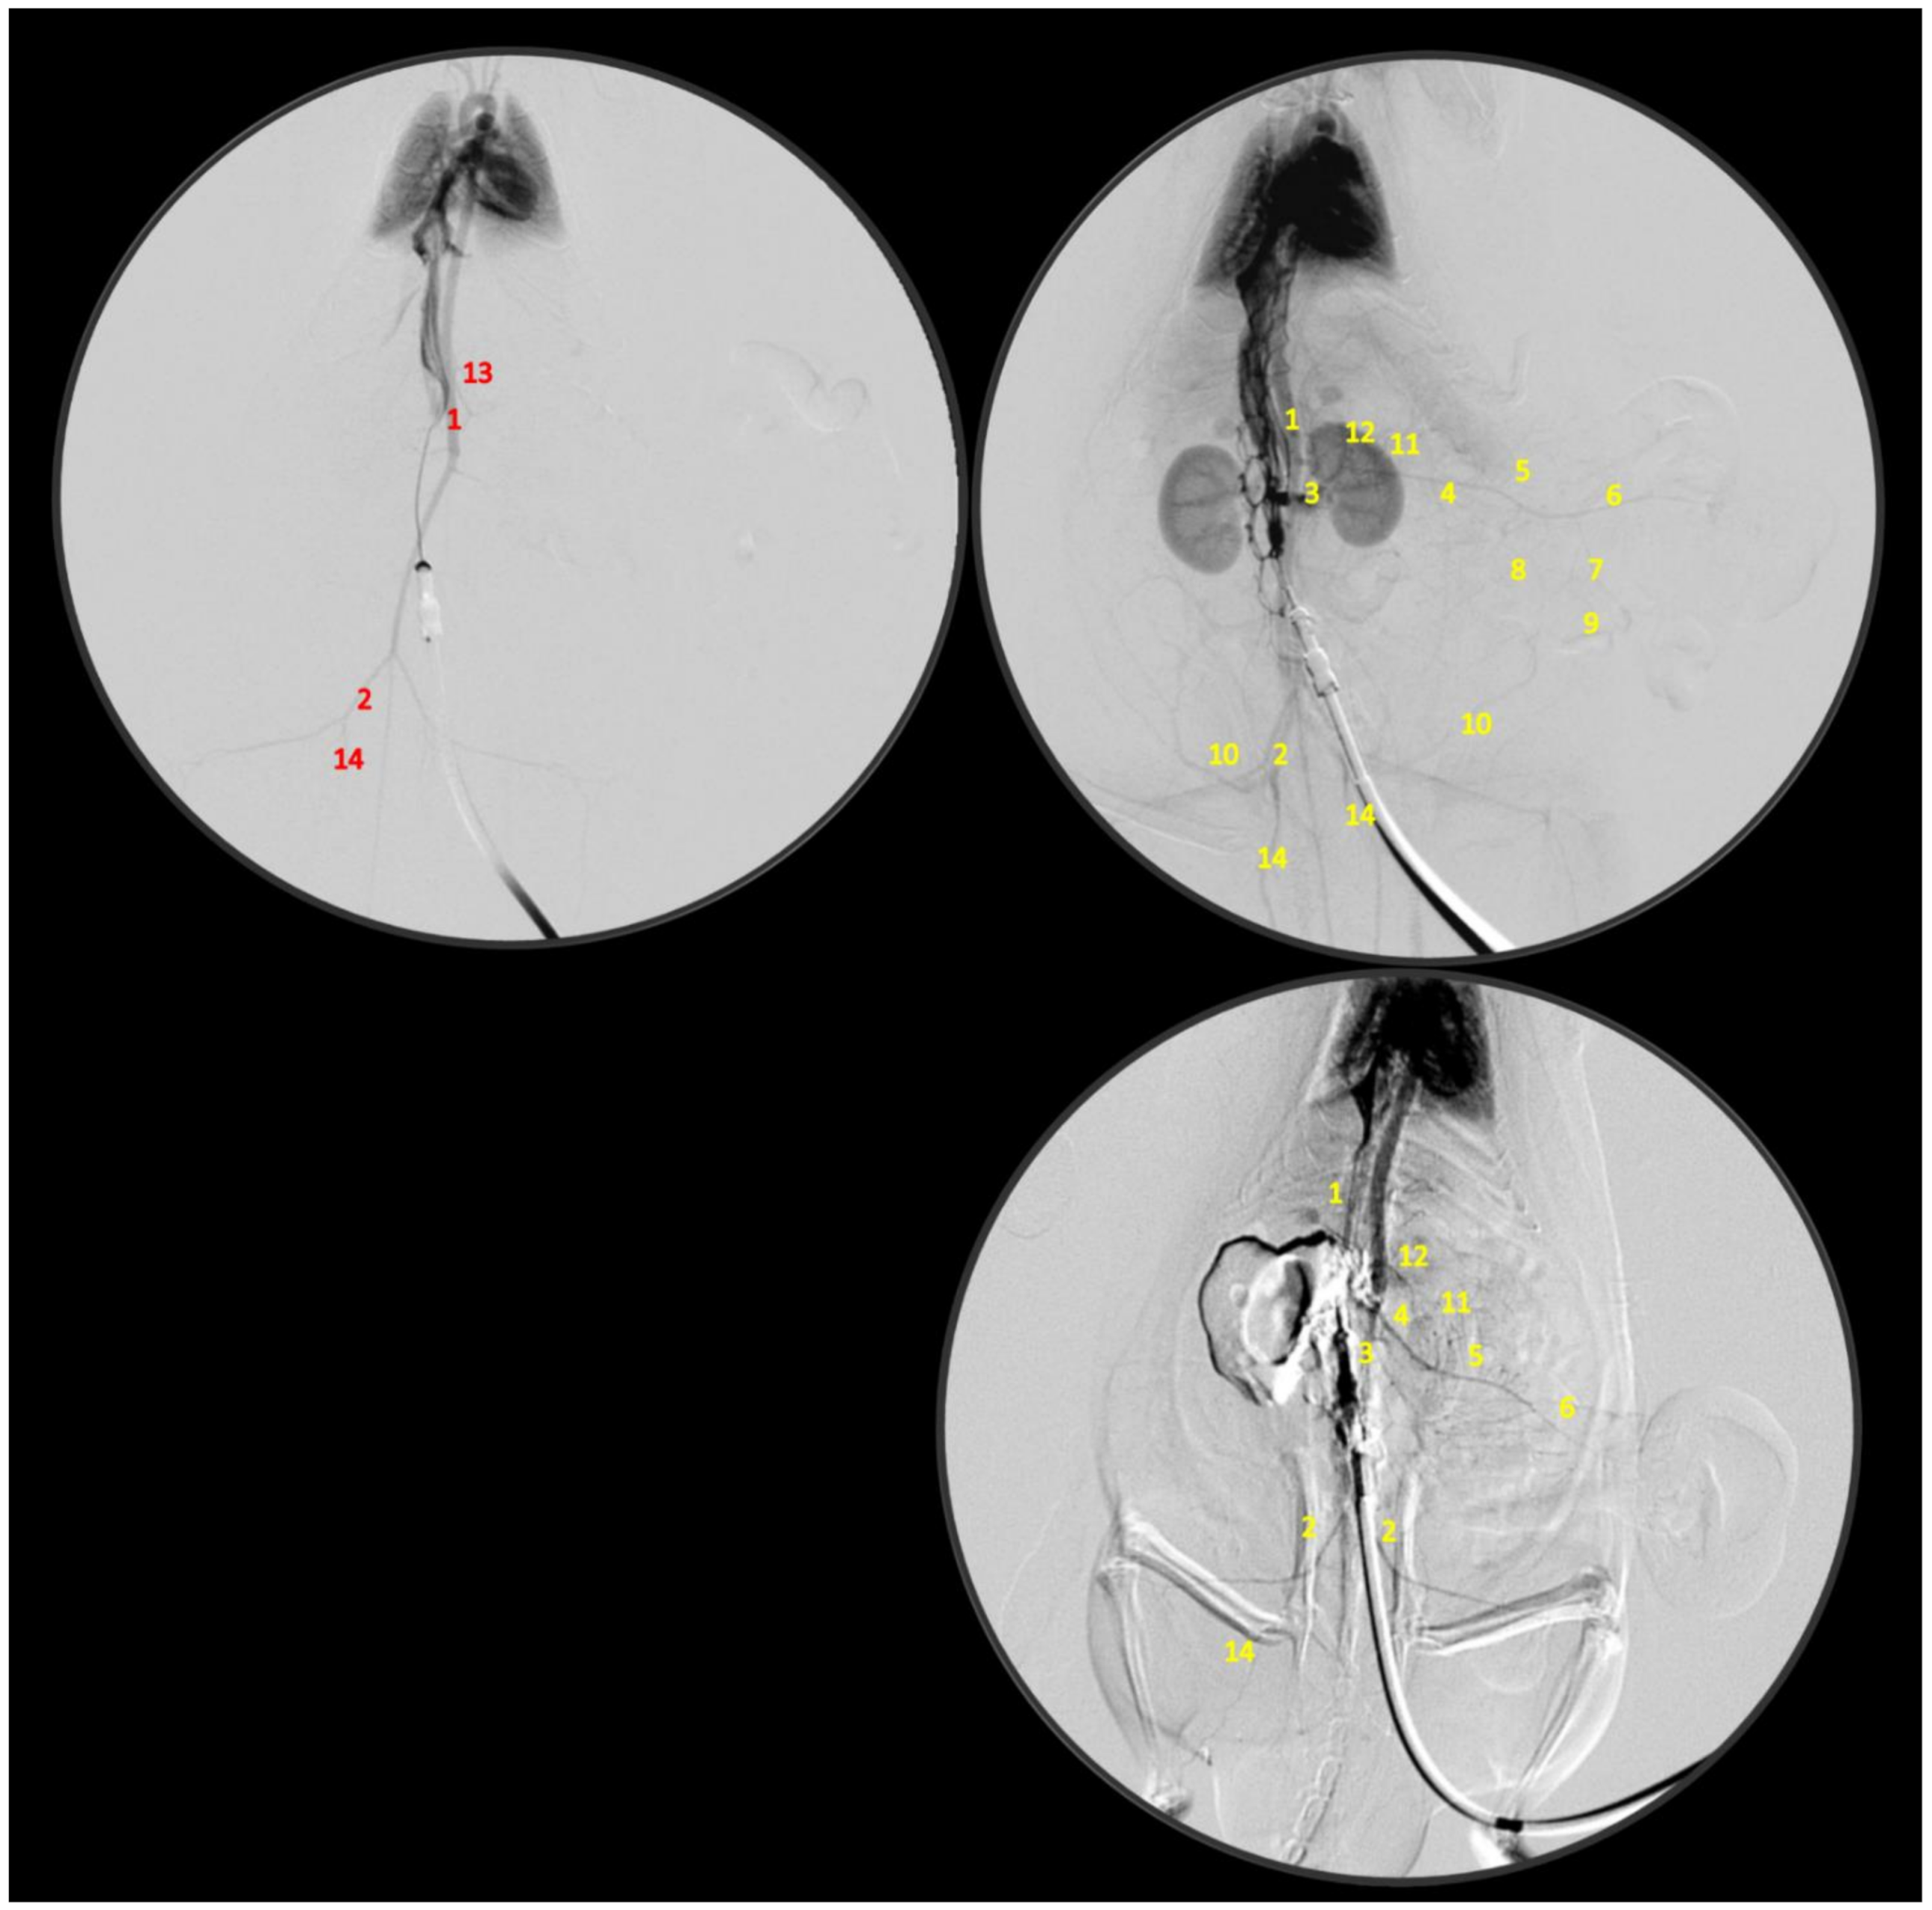

2.4. Venography

2.5. Superior Sagittal Sinus, Portal, Superior Mesenteric and Caval Vein and Abdominal Aorta Pressure Recording